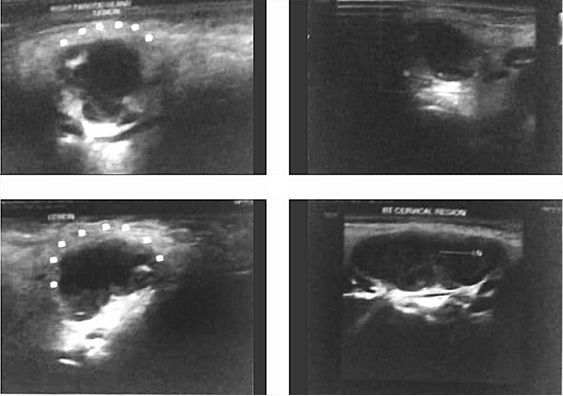

Routine blood investigations revealed haemoglobin 10.7 g/dl and total leucocyte count 15900/cumm with 55% neutrophils and 40% lymphocytes. ESR was 28 mm/hr. Ultrasonography of the swelling revealed intra-parotid collection measuring 21x17x18 mm in the superficial lobe with debris, suggestive of abscess (Fi­gure 2). It also showed multiple matted lymph nodes bilaterally (RT > LT), largest one measuring 39x21 mm, level-Ib (RT). A CT scan neck was not done in order to circumvent exposure to high radiation and also due to it’s poor specificity in differentiating tuberculosis from neoplastic lesions. FNAC was performed, and 3 ml pus was aspirated, which showed epithelioid granulomatous cells in the background of acute inflammatory exudates (Figure 3). Tuberculin test was highly positive at 18 mm. Chest X-ray was normal. The patient was started on Anti-Tuberculosis Therapy (ATT), with 4 drugs, i.e., Rifampicin, Isoniazid, Pyrazinamide, and Ethambutol for 2 months, followed by Rifampicin and Isoniazid for next 4 months. On follow-up after 15 days, swelling size had reduced significantly following spontaneous burst open of the swelling. The wound was expressed, cleaned and dressed regularly. The patient is on regular follow up and started gaining weight with healing of the rupture site.

gumbas-12.jpg

Figure 1

rentgen-1414.jpg

Figure 2